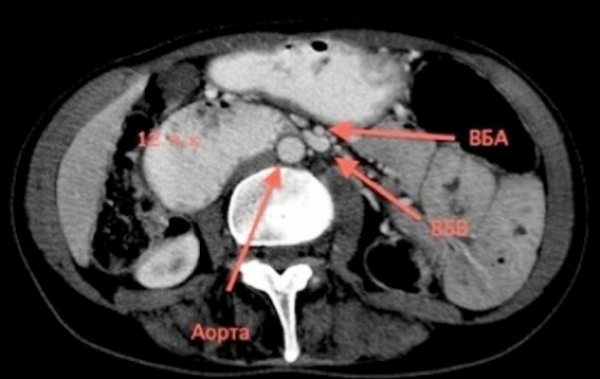

Верхняя брыжеечная артерия, без сомнения, играет наиболее важную роль в кровоснабжении пищеварительного тракта. Верхняя брыжеечная артерия отходит от передней полуокружности аорты обычно чуть выше отхождения почечных артерий, на уровне диска I и II поясничных позвонков. В своем начале она имеет диаметр 0,5—1 см. Артерия проходит непосредственно сзади шейки поджелудочной железы, а затем пересекает спереди 12-перстную кишку.

- КТ брюшной полости. Контрастирование пищеварительного канала с одновременной ангиографией абдоминальной части аорты назначается для верификации диагноза в сомнительных случаях. Исследование проводится для оценки стадии патологического процесса, измерения дуоденального просвета, величины угла, который образуют аорта и верхняя брыжеечная артерия.